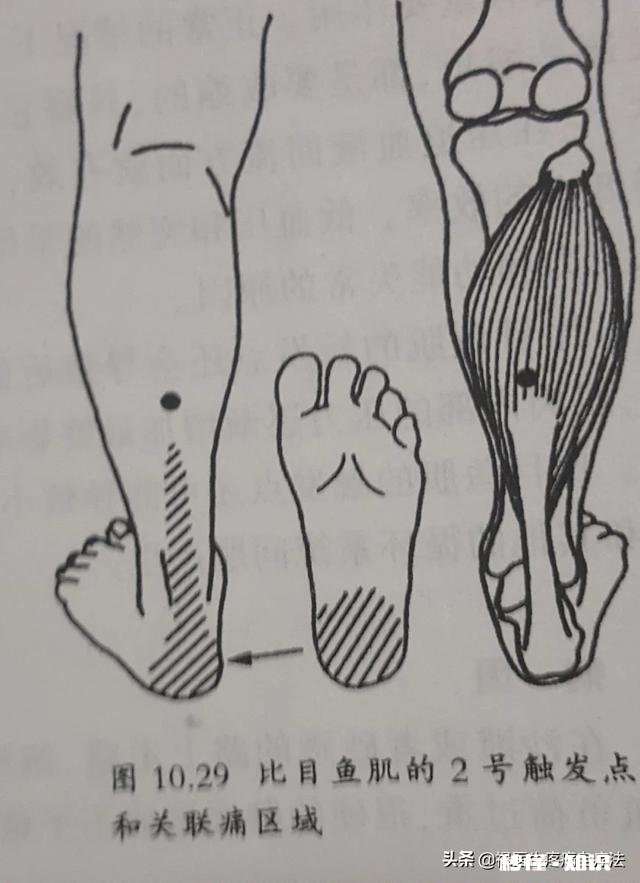

比目鱼肌损伤后会引起小腿后面、跟腱及足跟底部疼痛 。它是足跟底部疼痛的主要原因 。足底的足方肌损伤后会引起跟骨底部的疼痛,经常会被医生诊断为足底筋膜炎 。

文章插图